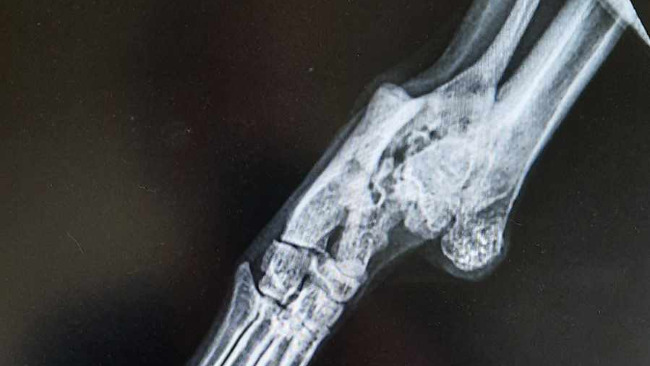

Kotka ma stare złamanie, musimy zebrać na tomograf, aby lekarz specjalista mógł zrobić zabieg.

Jedna z koteczek ma złamaną łapkę, w przyszłym tygodniu jedziemy z nią do ortopedy na konsultacje.

Mona byla na konsultacjach ortopedycznych, lekarz stwierdził, że złamanie dobrze się zrosło i nie ma potrzeby wykonywania zabiegu, z tego powodu zmniejszamy zbiórkę ❤️